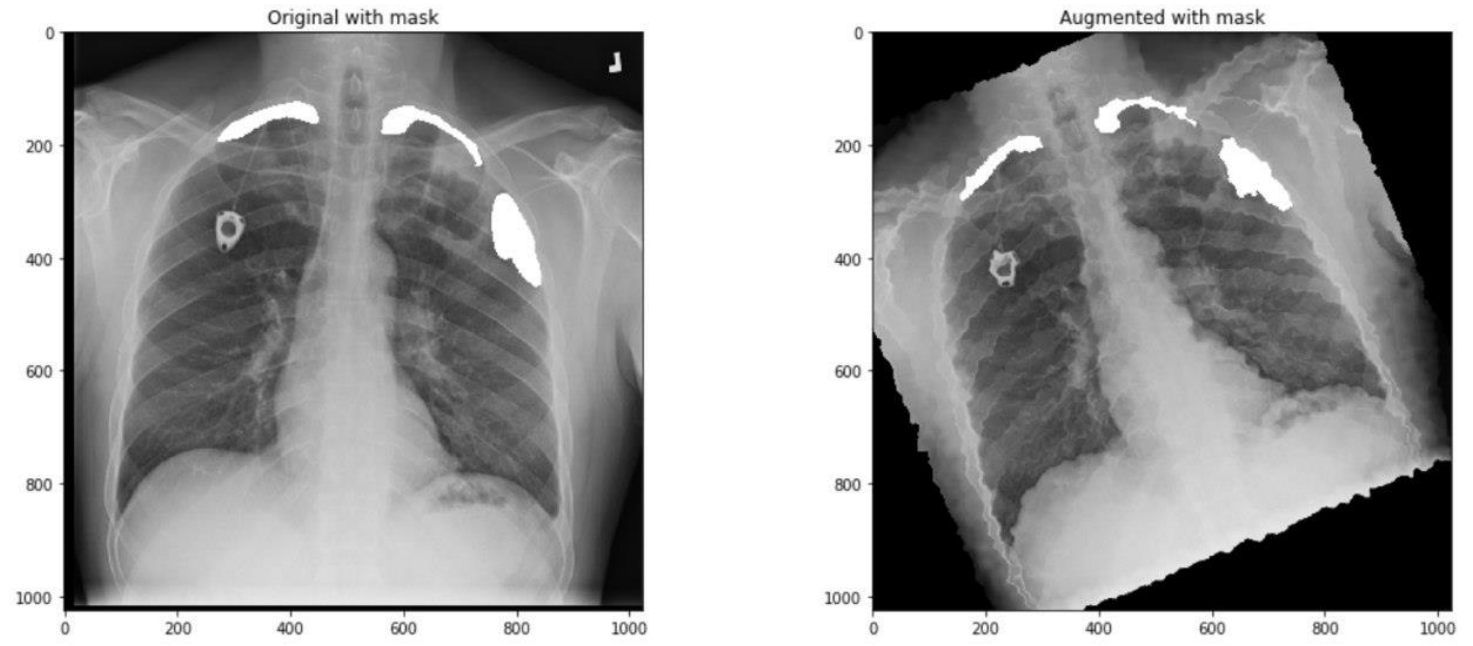

5 Post Proprecess

我们训练的分割模型输出每个像素的0-1概率,然后卡一下阈值,我们可以称这样的mask为basic sigmoid mask, 实际上医学图像中我们的分割目标也许并不存在,所以常用双重阈值(top_score_threshold, min_contour_area)的方法计算出mask并同时判断是否有分割目标(在本次比赛中我们分割目标是气胸),这种方法且称为doublet。其具体逻辑为:当大于概率阈值top_score_threshold的pixel数少于

min_contour_area,就将mask像素值全部置0,也就是认为此胸片没有气胸。简单画个示意图如下:

而作者在此基础上作了改进,使用了三重阈值(top_score_threshold, min_contour_area, bottom_score_threshold)的方法来达到相同的目标,且称改进后的方法为Triplet.其具体逻辑为:当大于概率阈值top_score_threshold的pixel数少于

min_contour_area,就将此mask pixel值全部置0,也就是认为此胸片没有气胸,然后再使用阈值bottom_score_threshold产生真正的mask。简单画个示意图如下:

最终作者通过搜索,分别获得了在validation和在Public Leaderboard上的最优参数:

- Best triplet on validation: (0.75, 2000, 0.3).

- Best triplet on Public Leaderboard: (0.7, 600, 0.3)

最后再附上作者的代码:

classification_mask = predicted > top_score_threshold

mask = predicted.copy()

mask[classification_mask.sum(axis=(1,2,3)) < min_contour_area, :,:,:] = np.zeros_like(predicted[0])

mask = mask > bot_score_threshold

return mask